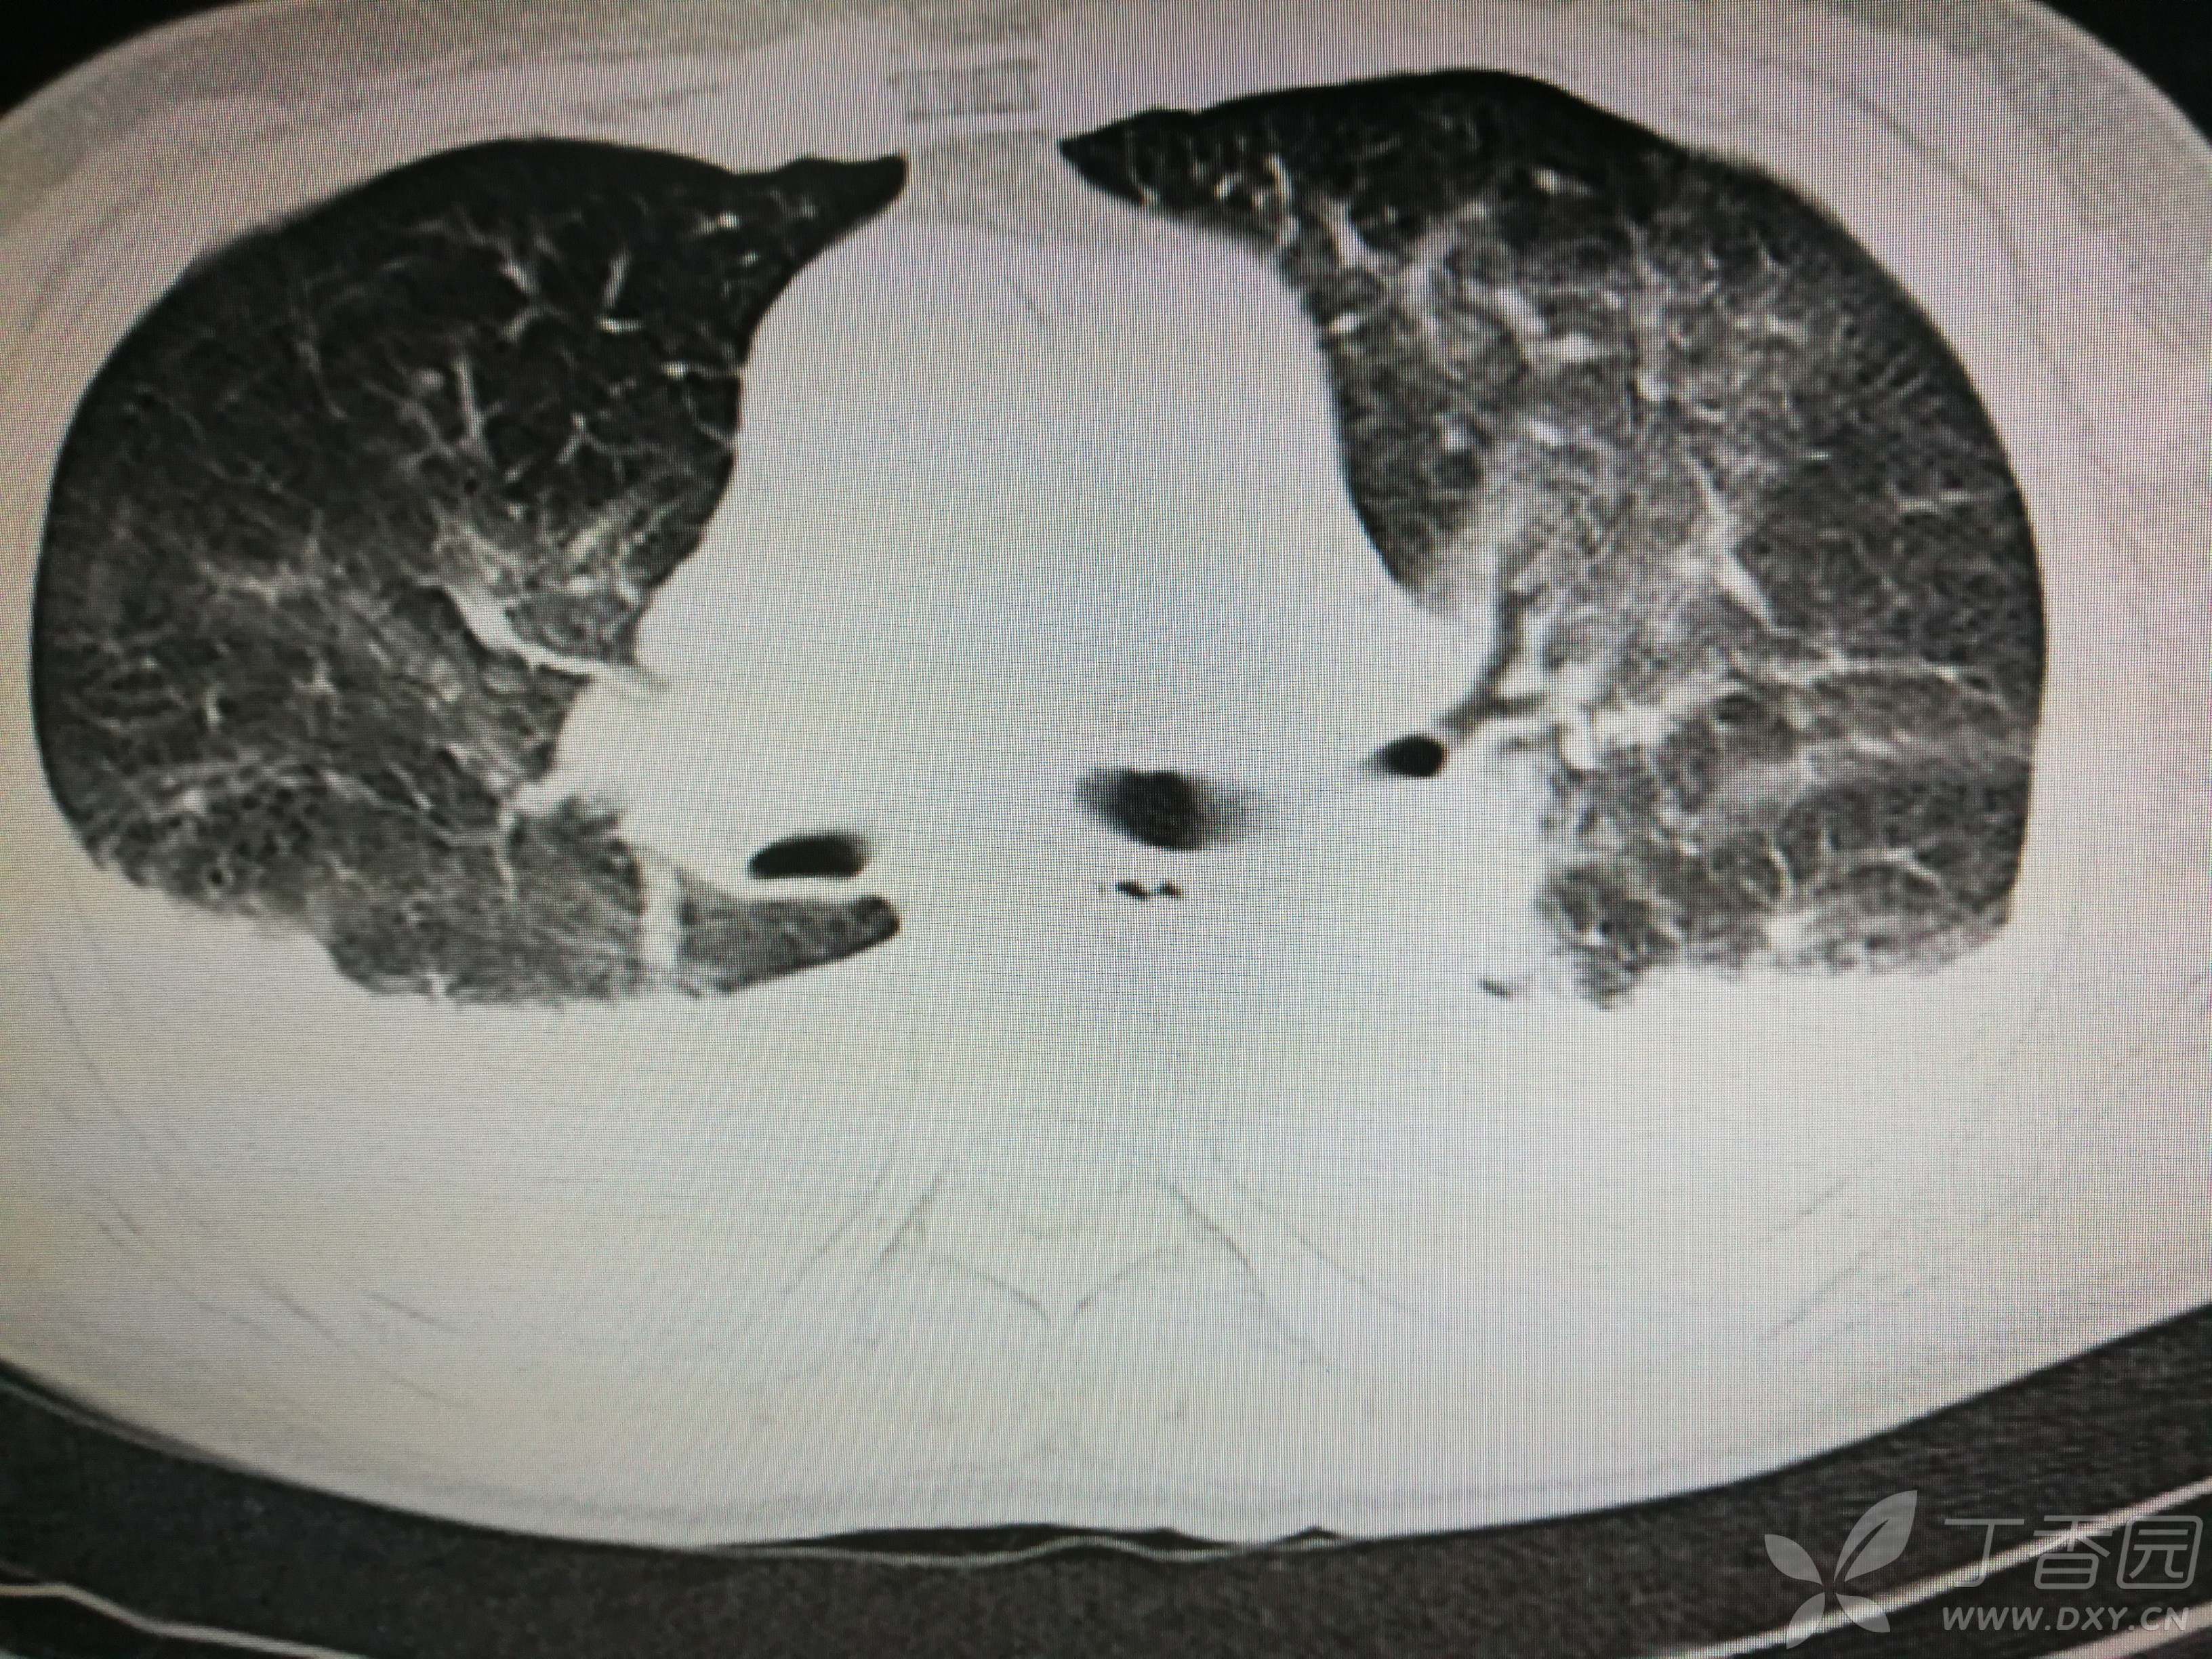

给予低分子肝素钙针抗凝、七叶皂苷钠针消肿及骨牵引固定等等治疗。入院后第四天行“左侧股骨下段骨折切开复位内固定术”(术前查双下肢彩超:双下肢深静脉血流通畅),手术顺利,术后予预防感染、预防血栓形成等治疗。术后患者无明显发热,生命体征平稳。术后第四天复查血常规:白细胞13.4×109/L,血红蛋白84g/L,血小板在正常范围。生化:白蛋白35.7g/L,余无明显异常。当天,患者开始出现轻度胸闷气急,可耐受。术后第五天患者胸闷气急加重,无胸痛,无背痛,无咯血,无意识障碍,无头晕头痛,无恶心呕吐等,急查凝血功能:纤维蛋白原降解产物12mg/L,D二聚体4000ug/L,余无明显异常。查动脉血气分析:pH7.52,氧分压62mmHg,二氧化碳分压30mmHg,碱剩余1.8mmol/L,乳酸1.0mm/L,血红蛋白86g/L。查胸部CT见下(先视频后图片):